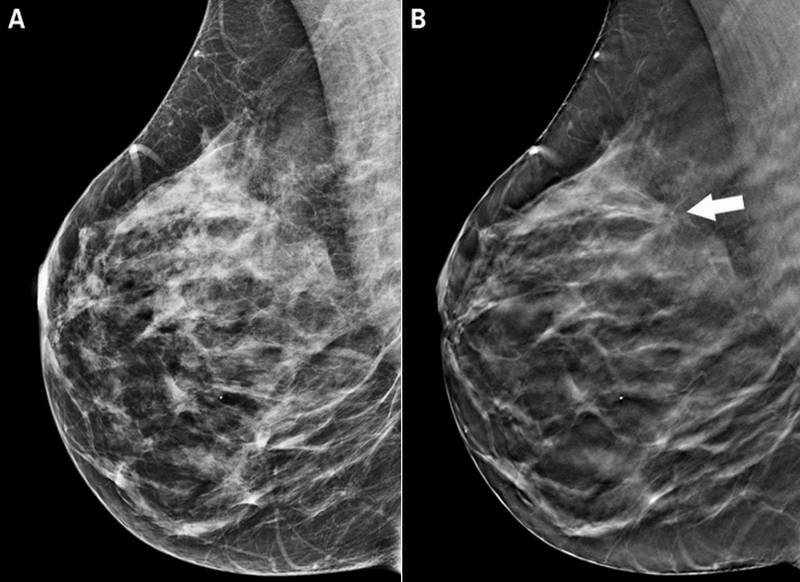

Феномен гипердиагностики в маммографии: примеры и иллюстрации

Раздел: Образы вокруг